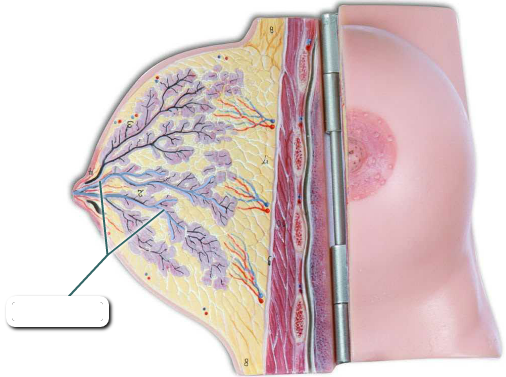

Mammary glands

Lactiferous duct

Areola